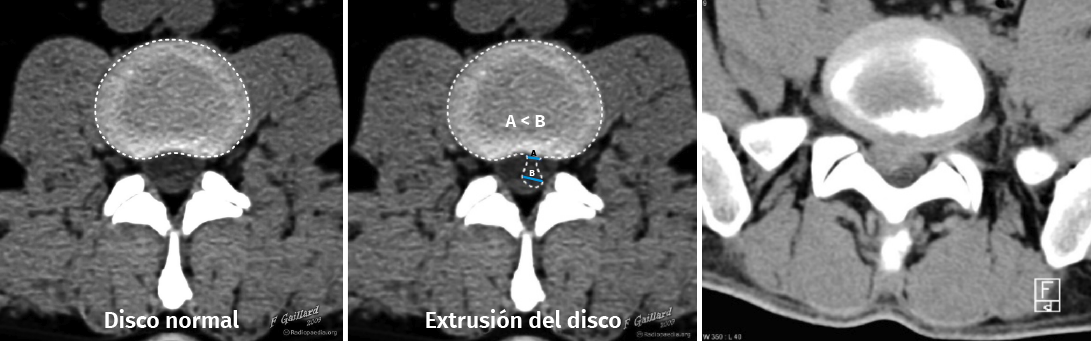

Figura 12. Tomografía axial computarizada de hernia discal. Reproducido de Gaillard(26).

Entre las principales indicaciones de la TAC, se incluirían la sospecha clínica de hernia discal (Figura 12)(26), la estenosis del canal vertebral lumbar, la fractura vertebral lumbar, los tumores vertebrales, la valoración posquirúrgica tras una cirugía de artrodesis vertebral lumbar y la sospecha de una sacroileitis en el contexto clínico de una posible espondiloartropatía inflamatoria. También es muy útil como herramienta auxiliar en determinados procesos diagnósticos, como por ejemplo en la biopsia de una zona sospechosa y en el diagnóstico postoperatorio de la correcta colocación de implantes en la columna vertebral.

Al igual que en la radiología simple, muchos pacientes asintomáticos presentan imágenes anormales en la TAC. En el estudio de Wiesel et al.(25), más del 35% de las TAC de columna lumbar en personas asintomáticas eran patológicas. Por ello, los expertos advierten de la necesidad de correlacionar adecuadamente los hallazgos de la TAC con la sintomatología referida por el paciente.

La sobrevaloración de las imágenes sin una correcta valoración clínica puede conducir a errores diagnósticos y terapéuticos de importancia, oscilando desde restricciones severas de la actividad física y laboral, indicaciones terapéuticas o rehabilitadoras inadecuadas, y hasta intervenciones quirúrgicas no indicadas.